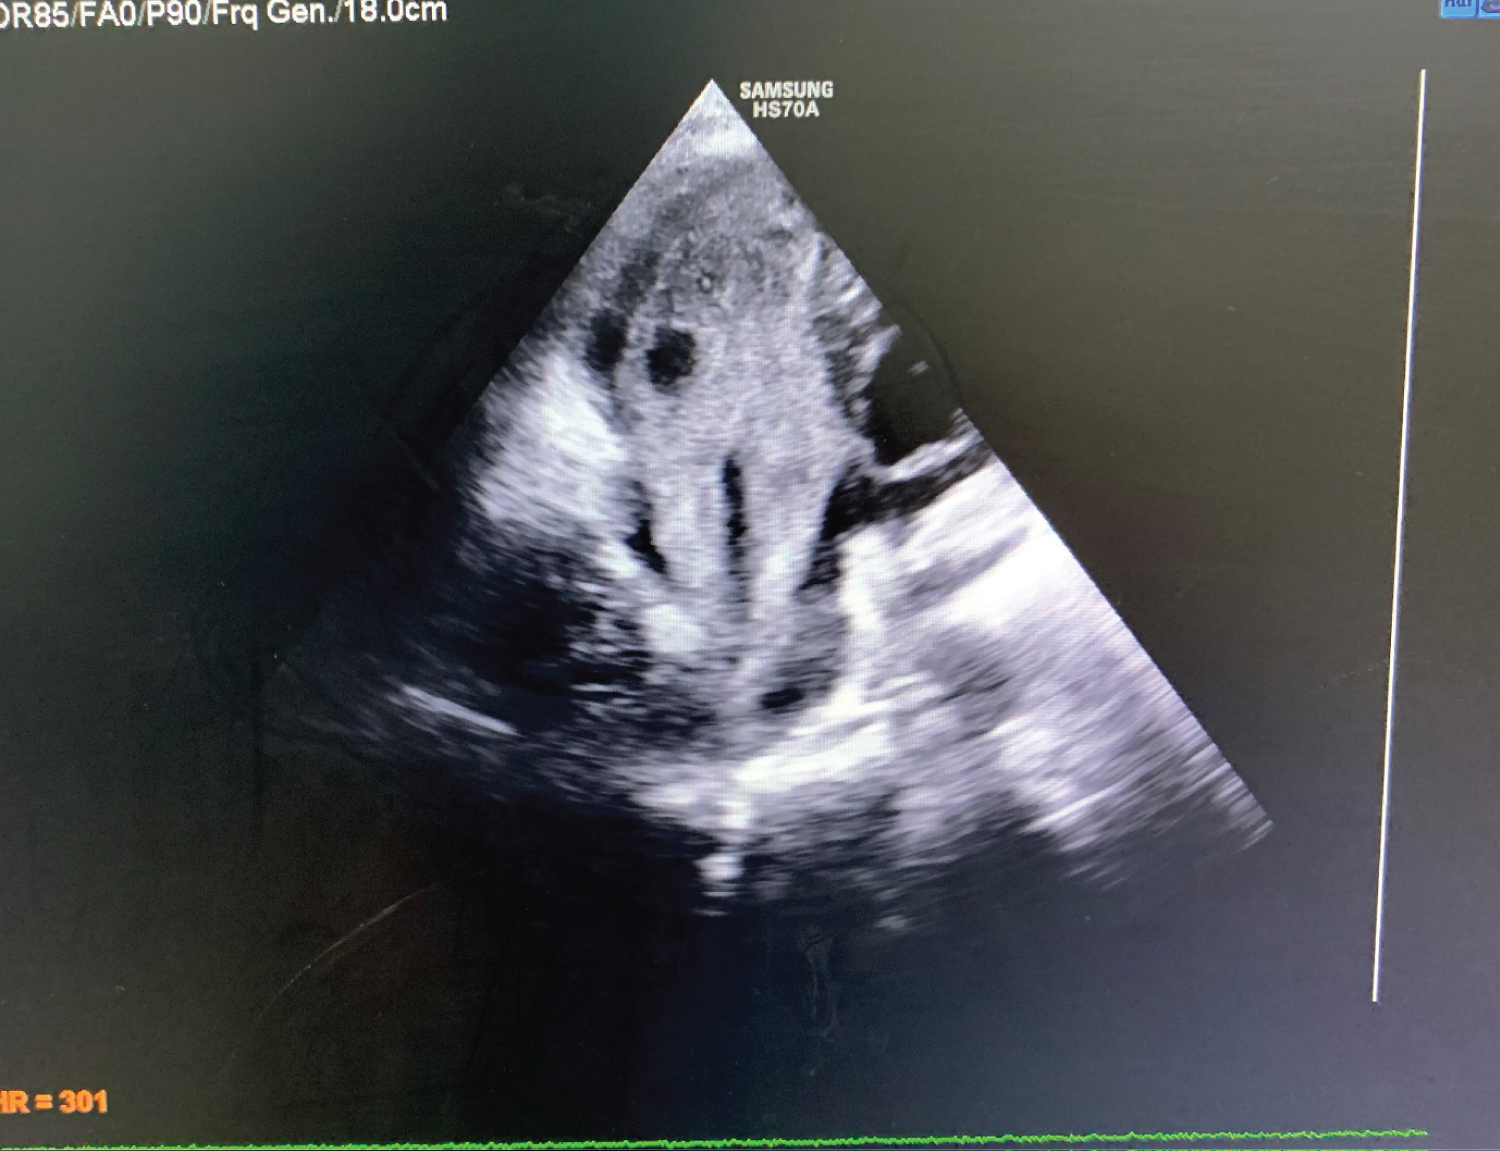

46-year-old gentleman admitted with shortness of breath and chest discomfort for last 6 months. He had no history of chest pain. He had history of flank pain for last few months along with occasional hematuria. He was taking self medications (analgesics) for these symptoms. On initial examination there was pallor and bipedal oedema. SpO2 was 96% in room air. Cardiovascular examinations revealed mid diastolic murmur in the mitral area without any radiation. Chest examinations revealed normal vesicular breath sound in both lung fields. Electrocardiogram (ECG) revealed sinus tachycardia with heart rate of 115 beats/min, regular in rhythm. Chest X-ray was advised which revealed no significant abnormalities. Echocardiogram was advised which revealed normal Left Ventricular systolic function. Right ventricle was filled with large echogenic mass extending to right atrium and beyond through inferior vena cava (Figure 1,2,3). It had cystic spaces clearly visible which initially seems to be tumour with cystic transformation. On further imaging the extension of the mass was clearly seen through tricuspid opening to right atrium and further into inferior vena cava. Considering the history of hematuria and flank pain he was advised for USG Whole abdomen, which revealed mas originating from right kidney. Now the diagnosis was evident as to be a large thrombus extending from renal vein to inferior vena cava and to right atrium to right ventricle.

Figure 1: Showing large echogenic mass filling almost whole of right atrium and right ventricle.